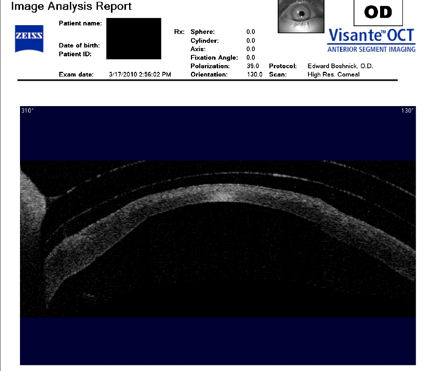

Следующие изображения были получены с использованием метода, называемого оптической когерентной томографией, или ОКТ. Прибор позволяет получить изображение в поперечном сечении путем сканирования передней части глаза (переднего сегмента) лучом света. Думайте об этом как об ультразвуке, использующем свет вместо звуковых волн для создания изображения живых тканей.

На изображении ниже представлен снимок роговицы в поперечном сечении после операции LASIK. Белая изогнутая линия вверху - это передняя поверхность твердой контактной линзы. Следующая едва заметная белая линия - это задняя поверхность линзы. Следующая область, которая имеет зернистый вид, - это пространство между хрусталиком и роговицей, заполненное физиологическим раствором. Роговица имеет классические признаки эктазии - истончение, выпуклость и неправильную форму.